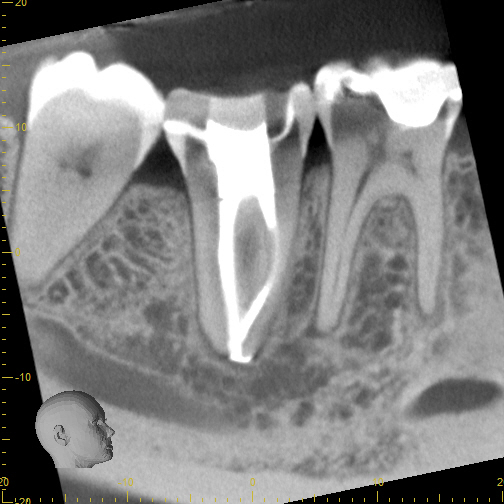

Case 5

Another case showing dramatic healing from root canal treatment. This patient had chronic sinus inflammation that never seemed to heal. The cause--an infected tooth. The top row images show both an erosion of the sinus floor from the tooth roots into the sinus cavity, as well as significant inflammation (swelling) of the sinus soft tissues that line the sinus. During retreatment I was able to find and clean all the canals, including one canal that was previously missed during the first root canal (I did not treat the original root canal). The bottom row images (one year later) shows complete re-establishment of the sinus floor (the bone that separates the sinus from the teeth) and complete resolution of the sinus swelling. There is no more infection. This retreatment case shows that even if a root canal treatment has failed, it can still often be saved. Always seek evaluation from an Endodontist before pulling out a "failing root canal"!